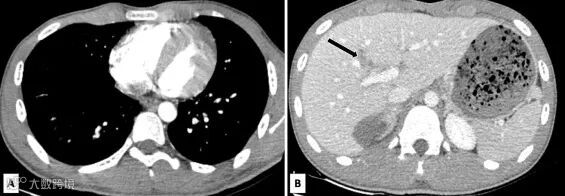

30分钟后,该患者重新进行腹部CT增强扫描。在第二次腹部CT上,心脏的功能性血泵正常,并可以观察到肝脏损伤(图2)。

pic.2

(A) CT增强动脉期显示2个心室和主动脉均匀强化。

(B) 门静脉期显示肝脏内有少量强化且不规则的区域,与撕裂伤相符(黑色箭头)。